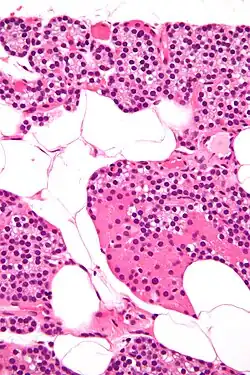

Buňky krevní a imunitní

- červená krvinka

- megakaryocyt

- neutrofil

- eosinofil

- basofil

- žírná buňka

- T-lymfocyt

- B-lymfocyt

- NK buňka

- různé kmenové a progenitorové buňky krevních a imunitních buněk v různém stupni diferenciace